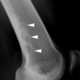

Lucent bone lesion with sclerotic rim

May Be Caused by